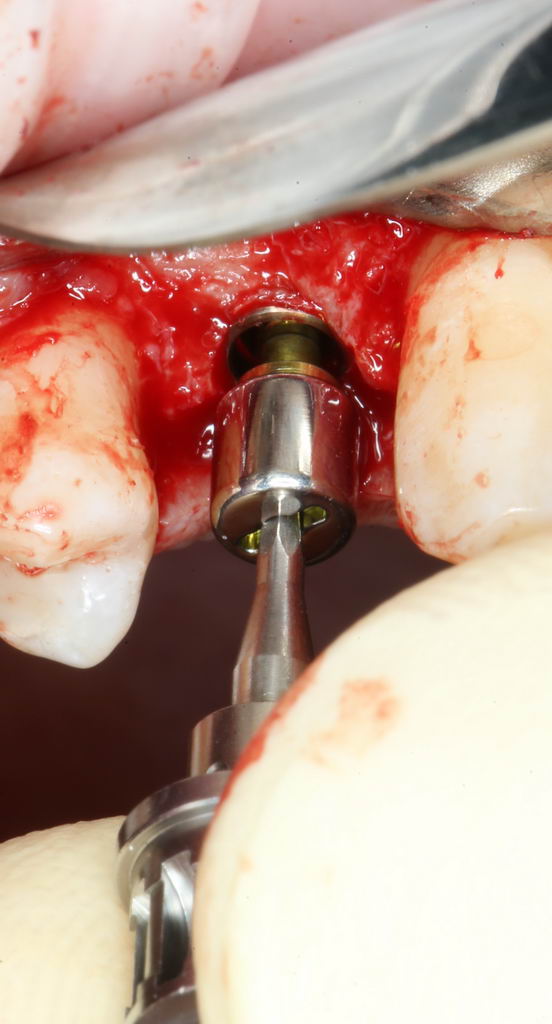

Установка имплантата.

XiVE — одна из наиболее совершенных и универсальных имплантационных систем. В ней продумано всё. Даже упаковка:

В комплекте поставки есть всё, что нам необходимо даже для немедленной нагрузки: помимо имплантата, в коробке есть заглушка и временный абатмент TempBase с винтом. К сожалению, ни тем, ни другим мы не воспользуемся. Как говорится, не в этот раз.

Имплантат нужного размера (3.8х11 мм) фиксируется на гексагональном ключе, после чего устанавливается в подготовленную лунку:

Превышение усилия — это повышение нагрузки (читай, излишняя травма) на костную ткань вокруг имплантата. Что, в свою очередь, ведёт к периимплантиту или отторжению. Вот почему важно контролировать и регистрировать крутящий момент в процессе установки.

Как видите, в нашем случае он не превышает 25 Нсм — оптимально даже для немедленной нагрузки. Это значит, что необходимые параметры имплантации выдержаны правильно.